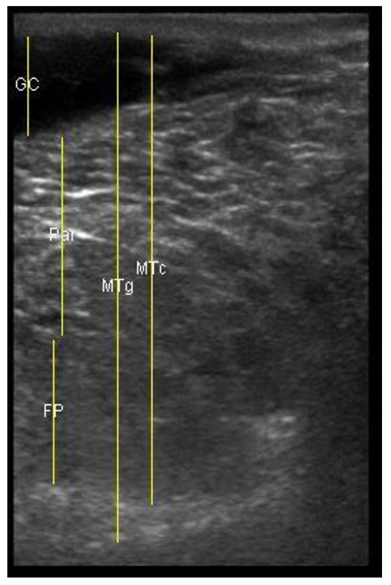

| 109 days of pregnancy (P109) Scanning depth 4.7 cm | ![]() | ![]() | MT generous: 36.8 mm MT conservative: 27.2 mm Gland cistern: 4.7 mm Parenchyma: 15.4 mm Fat Pad: 5.5 mm |